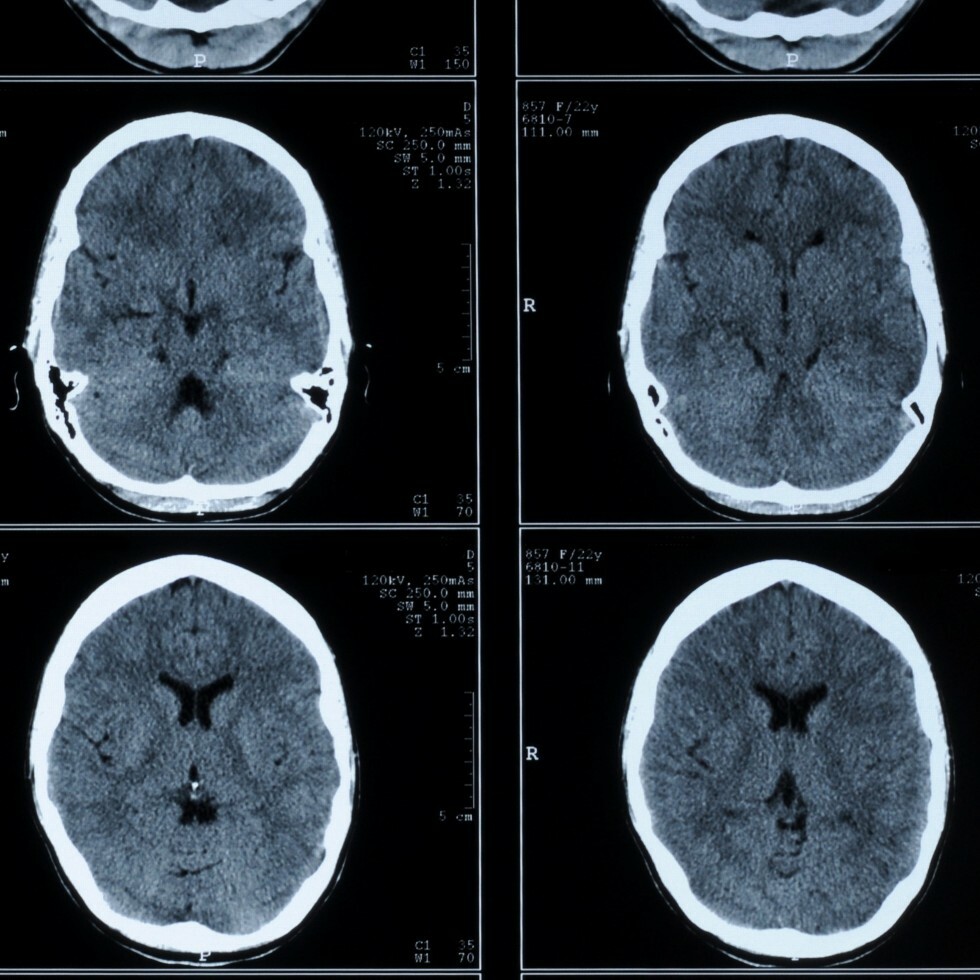

What is a CT of the head?

A CT scan of the head is a type of scan that uses special X-ray equipment to obtain images from all angles of the head. It then joins the images together to show a cross-section of body tissues and organs. The scan provides detailed information on head injuries, stroke, brain tumors, and other brain diseases.

Why might my doctor recommend a CT of my head?

A CT of the head may be recommended for many different reasons. Your doctor may recommend a CT of the head if you experience severe headaches or if he or she is questioning your risk of stroke, a mass or tumor, or other neurological symptoms. A CT of the head can detect a variety of problems within the brain, including: bleeding, blood clots, brain damage, skull fractures, brain tumors, and diseases or malformations of the skull. The procedure also is used in planning radiation therapy for cancer of the brain or other tissues.